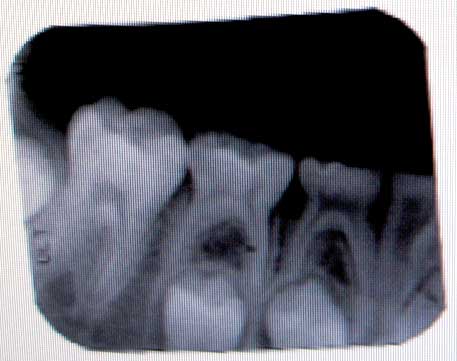

Fact: Jon’s progress on his baby teeth—or if your mail-order DDS diploma arrived today, deciduous teeth—is very slow. This is not a panic to us, as one of our nieces has this issue too, and everything is fine, just slower.

The oral surgeon, Dr. Nish, thinks more removals are coming in the future, and that the eye teeth don’t buy too much more room. The removal of four teeth alone will require Jon to be anesthetized, and although anesthesia is relatively safe, there is always risk. Since he believes that Dr. Dagys is going to have him remove more teeth in the future, he feels that he should remove three teeth per quadrant (=12) in one fell swoop and Dr. Dagys can fit Jon with temporary dentures to fill the immense chewing surface gap. Mind you, Dr. Nish is a bit concerned by Jon’s late schedule, and admits that there’s a risk of Jon’s permanent teeth never emerging, despite their existence on x-rays.

Dr. Dagys has not told us about further removals, and when you combine that with the low, but real, risk of lack of the emergence of the permanent teeth, we think 12 at a time is a tad on the extreme side.